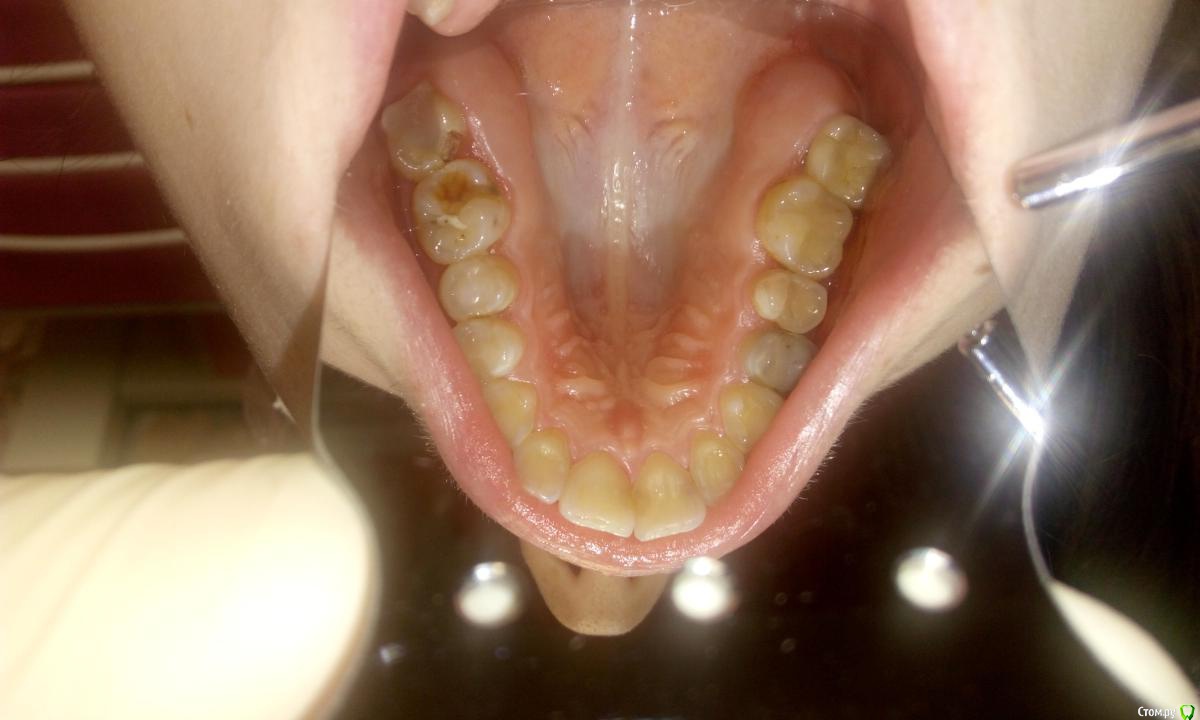

ZubFairy Опубликовано 3 апреля, 2014 Поделиться Опубликовано 3 апреля, 2014 (изменено) Уважаемые доктора,каков Ваш план лечения таких зубов 46,47? Изменено 3 апреля, 2014 пользователем ZubFairy 1 1 Ссылка на комментарий

ZubFairy Опубликовано 3 апреля, 2014 Автор Поделиться Опубликовано 3 апреля, 2014 Фото плохого качества,если получится перефоткаю . Оба зуба не беспокоят.Мой план лечения:перепломбировка каналов в 46,пломба ,коронка . А вот с 47 сложно. На данный момент он пациента не беспокоит,но 2 недели назад были сильные боли на фоне простуды. Сейчас всё ок,перкуссия и пальпация безболезненны. Эндомотора у меня нет,файлы обычные,гутта ассорти,эндометазон.(и так на 250 км.вокруг),поэтому послать к другому доктору не получится. Скажите свой план лечения таких зубов? Ссылка на комментарий

Kolchanov Опубликовано 5 апреля, 2014 Поделиться Опубликовано 5 апреля, 2014 Почему семерку-то все приговорили? Что там с ней? По этим снимкам вообще ничего нельзя сказать Ссылка на комментарий

ger_berra Опубликовано 5 апреля, 2014 Поделиться Опубликовано 5 апреля, 2014 Почему семерку-то все приговорили? Что там с ней? По этим снимкам вообще ничего нельзя сказатьЯ согласна на счёт качества снимков,но мне не нравки тень в бифуркации в твердых тканях. Ссылка на комментарий